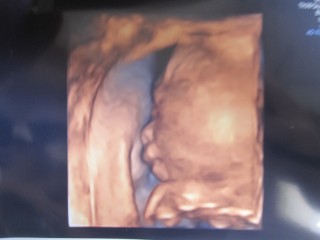

この日は胎児超音波スクリーニング検査をして異常なく3D4Dを両方やりました。 性別は女の子と言われました♡ 男の子希望だったけど4Dで動画を見てたら可愛くて 五体満足健康ならどちらでもよくなっちゃいました♪

この時女の子って分かりました♡

まだ小さくて脂肪も全然ついてないのに赤ちゃんって形に感動です‼︎